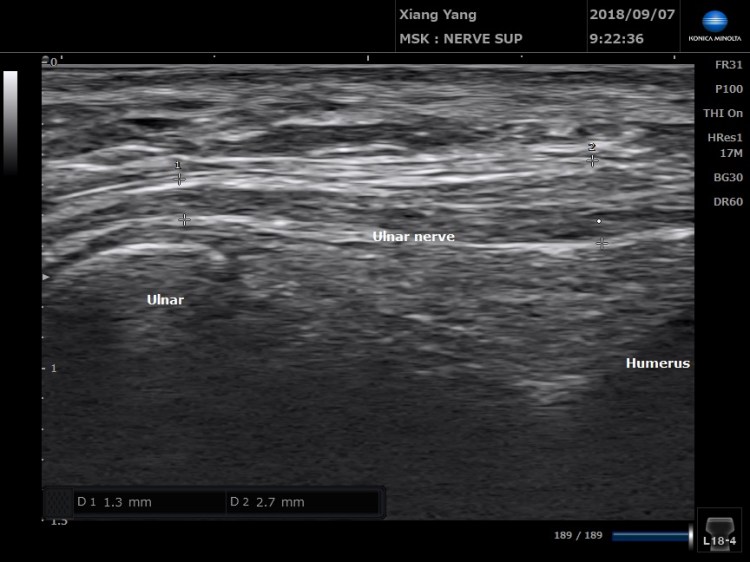

把尺神經拉成長軸,就可以看到哪個位置比較腫脹。